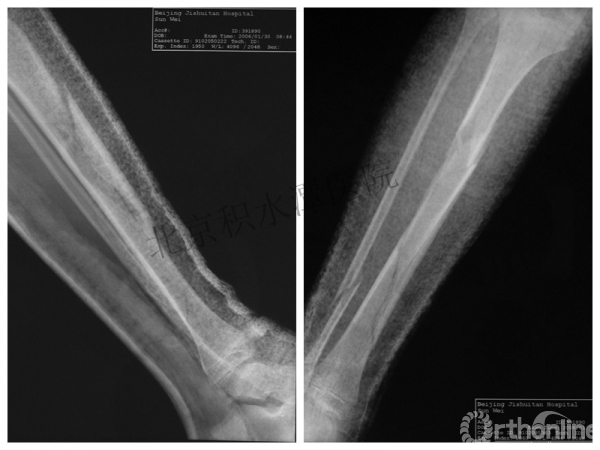

男孩、9岁,滑雪受伤,胫腓骨螺旋形骨折(粉碎性)

手法整复,石膏制动!

整复后7天

儿童具备强大的愈合潜力,同样也有极强的塑形能力

某种情况下,The best treatment is no treatment! 最佳治疗反而是不治疗!因为很多骨折依靠儿童强大的塑形能力和特点完全可以得到满意的结果!